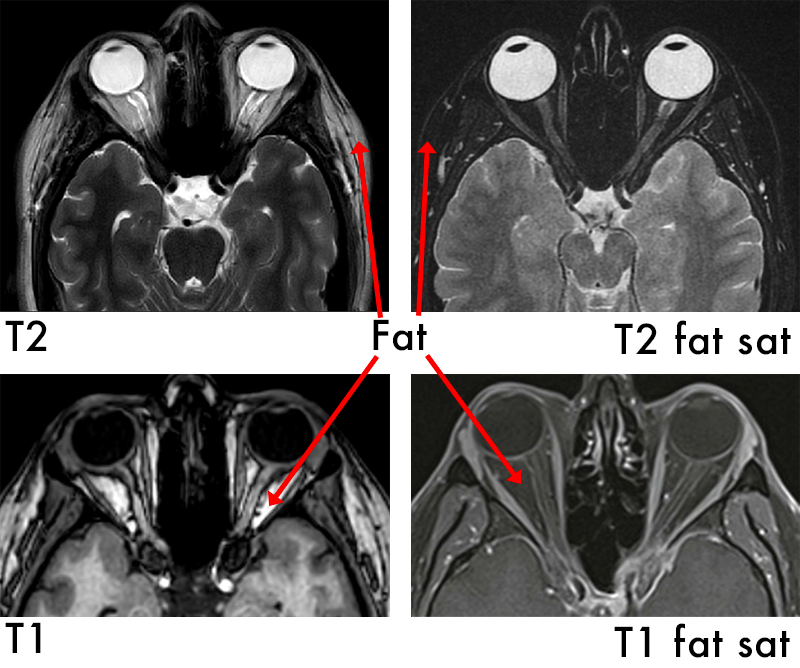

Cholecystitis on US

Thick Gallbladder walls

Oedematous wall (swollen)

Vascular wall

Murphys positive (hand pressed on gallbladder area produces pain on inspiration)

Fluid surrounding Gallbladder

Stones in Gallbladder

Contracted gallbladder

Wall Echo Sound sign (contracted gall bladder filled with stones)

Choledocholithiasis on Ultrasound

Choledocholithiasis

Bile duct >6mm

Intrahepatic duct dilatation

Distended Gallbladder

+/- pancreatic duct dilation

Stones in gallbladder